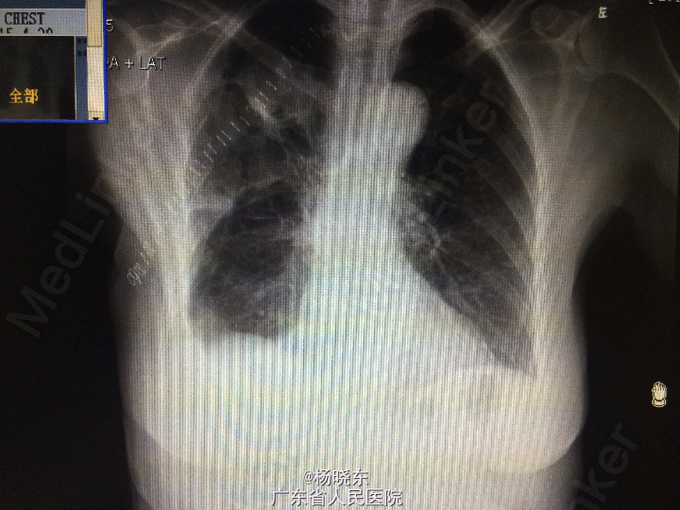

主诉:反复胸背痛1年,加重1月。 病史:患者1年前无明显诱因出现右侧胸背痛,性质为隐痛,无向周围放射。遂至当地医院门诊就诊,查胸部CT,考虑“胸膜肿瘤”,建议手术处理,但患者拒绝未予治疗,症状持续数天后自行消失。后间断出现类似症状,但均可忍耐。1月前患者自觉右上肢上抬及抬举重物时右侧胸背痛明显,不伴有其余部位牵涉痛,未予重视。近1周来,患者自觉症状加重,疼痛致右上肢不可上抬,弯腰时加重,平卧时可缓解。现为进一步手术治疗入院,无发热,无头晕、头痛,无咳嗽、咳痰,无气促、心悸,无恶心、呕吐,无腹痛、腹泻,无皮疹、无双下肢浮肿。自起病以来,精神、睡眠可,食欲可,二便正常,体重近1月下降2kg。

查体:右侧胸肋部及肩胛区压痛明显。 辅查:胸片,CT。

诊断:胸膜间皮瘤 处理:右侧胸膜肿瘤切除术

术中病理显示为结核脓肿,改行右侧胸膜结核性脓肿扩大清除术+右肺楔形切除术。 术后予加用异烟肼+利福平+乙胺丁醇联合抗结核治疗。